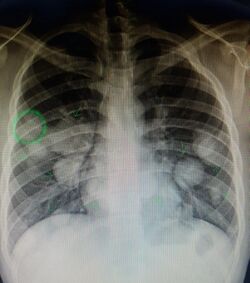

Metastatic cancer in the lungs